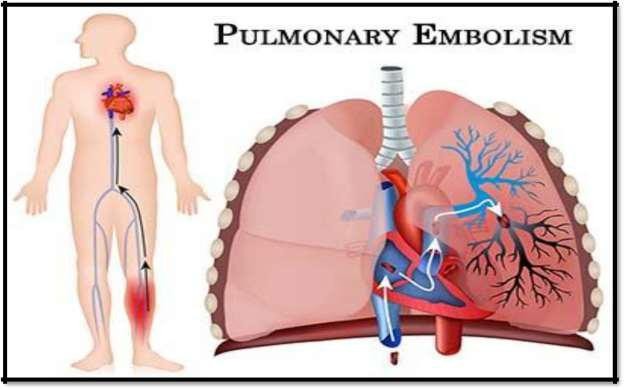

Pulmonary Embolism

Pulmonary embolism is a blockage in the pulmonary arteries in your lungs. Usually, a pulmonary embolism is caused when blood clots from the legs and sometimes other areas of the body (deep vein thrombosis) travel to the lungs.

A pulmonary embolism can reduce or block the blood flow to the lungs, becoming a life-threatening condition. With prompt and expert treatment, the chances of this condition resulting in death are greatly reduced. One of the best ways to prevent a pulmonary embolism is to take adequate measures to prevent blood clots in your legs. If blood clots are formed, quickly eradicate them.